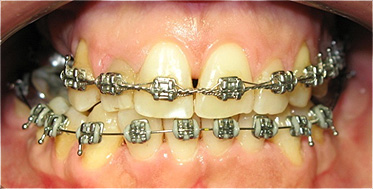

Após dois anos de tratamento ortodôntico.

![]() |